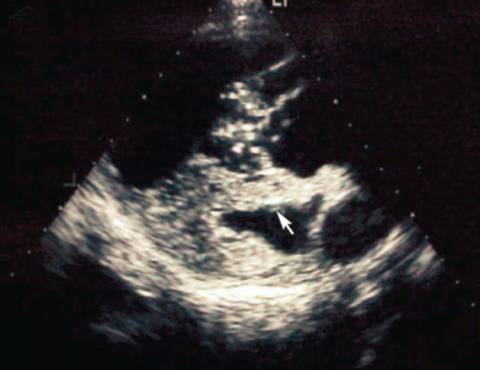

当右心舒张末期内径及心室壁厚度增加时,超声心动可以敏感的检测到右心功能异常(比如,右心扩张)。在有些病例中,可以看到肺主动脉及右心的心丝虫(图5)。超声心动可以检测虫体数量多少,三尖瓣返流以及肺动脉高压的严重程度。超声心动还可诊断腔静脉综合征。

图5 心丝虫病例超声心动。可以看到心丝虫成虫。